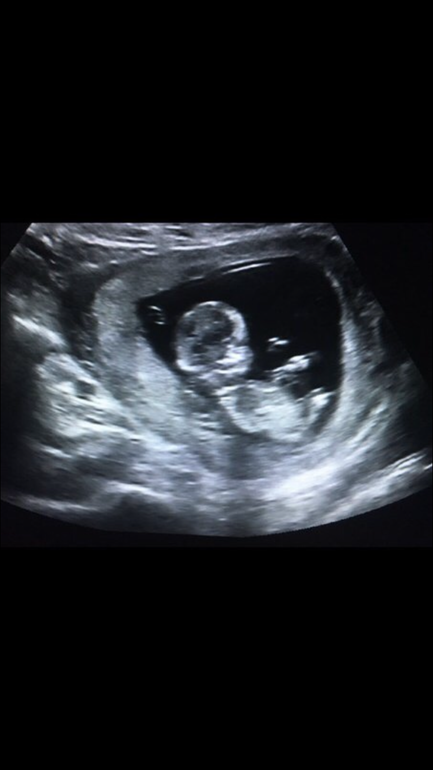

Вопросы про УЗИ, обследования и анализы: что, где, как, когда?Добрый день! Сегодня у меня был скрининг, срок 12 недель. Сильно волновалась, поднялось давление, и думала, сердце выскочит из груди, пока лежала на кушетке. Когда показали на экране малыша- успокоилась. Но ничего не смогла спросить. Из головы все вылетело. И врач не многословен был. Сказал, по УЗИ все хорошо. Показал ручки, ножки, сказал,что есть носовая косточка. И все. А я даже ничего не спросила, улыбалась до ушей и на монитор смотрела. А теперь думаю, что надо было узнать про воротниковую зону, про срок. Как у вас проходил скрининг? Какие вопросы задавали? Или что вам говорил врач после УЗИ?

Разрешили сфоткать с монитора.Это 12 нед было